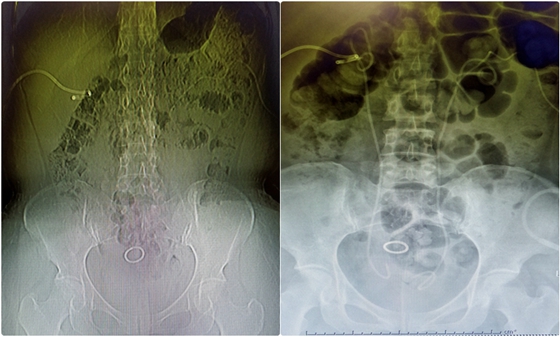

术前与术后CT对比图

鉴于余女士宫颈癌未行手术治疗,肿瘤压迫双侧输尿管引起双侧输尿管梗阻,而且行放化疗后,膀胱粘膜放射后炎症改变,易出血,病情十分复杂,但患者及患者还是强烈要求拔除双侧造瘘管。顿金庚主任立即组织科室全体医生讨论研究他的病情并制定详细的治疗方案及应急预案。根据余女士CT检查结果及身体情况,于1月26日上午9时在顿金庚主任指导下,蒋欣杰副主任医师及孙吉住院医师为患者顺利实施了输尿管镜下双侧D-J管置入术,术中清除膀胱内血凝块后,反复寻找,将患者几乎闭锁的输尿管开口找到,并顺利放置了双侧D-J管。术后复查双侧D-J管位置良好,术后2天夹闭双侧肾造瘘管、取掉了“随身尿袋”,患者小便恢复正常,清亮,于术后第5天完全康复出院。